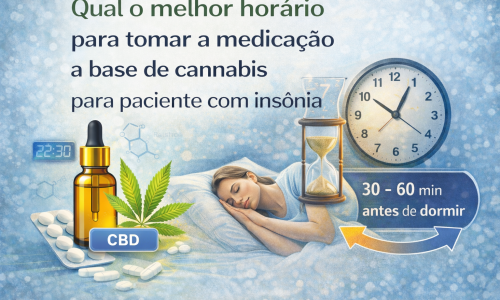

Estudos científicos indicam que o sistema endocanabinoide participa da modulação da dor muscular e articular, além de influenciar processos inflamatórios locais e a resposta ao estresse, fatores diretamente relacionados à disfunção temporomandibular.

Além disso, quadros crônicos de DTM frequentemente apresentam envolvimento de mecanismos de sensibilização central, o que pode dificultar a resposta a terapias convencionais isoladas. Nesses casos, estratégias terapêuticas complementares voltadas à modulação da dor e da inflamação vêm sendo estudadas como parte de um plano clínico individualizado e multidisciplinar.

O uso terapêutico da cannabis ainda não é um substituto para tratamentos odontológicos consagrados e deve ser integrado ao plano clínico, respeitando critérios éticos, científicos e legais. Consulte sempre um profissional.